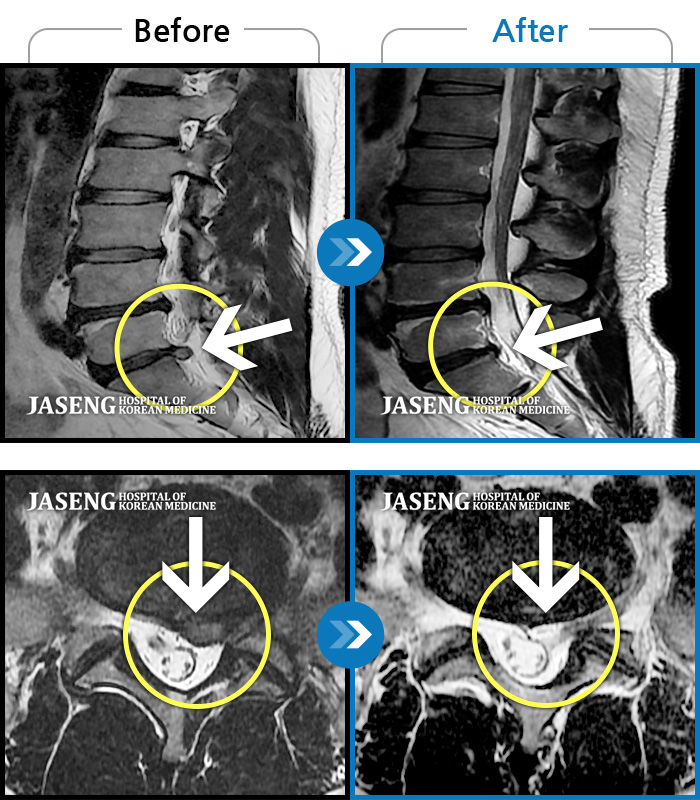

1,228건의 MRI 전후 사진으로 터진 디스크 흡수 사례를 확인하세요.

하지 저림과 통증이 개선되어서 일상생활이 너무 즐겁습니다. |

| 병의원명해운대 | 질환명허리디스크 | 담당의김상돈 원장 | 날짜2025.02.05 | 조회수23,808 |

[해운대] 23.09.18~25.01.27

※ 환자분에게 사전 동의를 받아 동일 조건에서 촬영되었으며, 개인에 따라 치료 후 부작용이 발생할 수도 있으니 사전에 의료진과 상담 후 치료를 진행하시기 바랍니다.